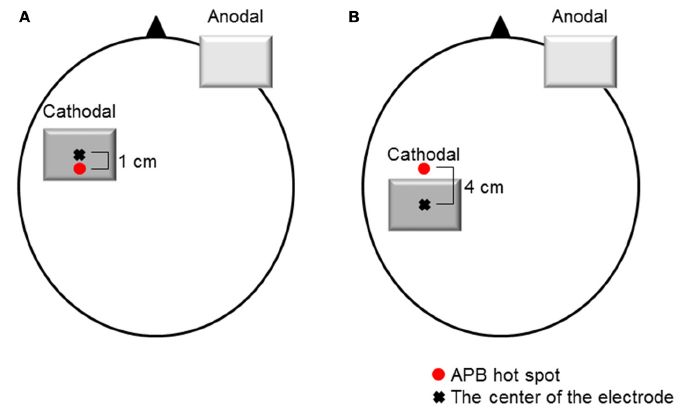

Sasaki R, Miyaguchi S, Kotan S, Kojima S, Kirimoto H, Onishi H. Modulation of cortical inhibitory circuits after cathodal transcranial direct current stimulation over the primary motor cortex. Frontiers in Human Neuroscience. 2016; doi: 10.3389/fnhum.2016.00030.